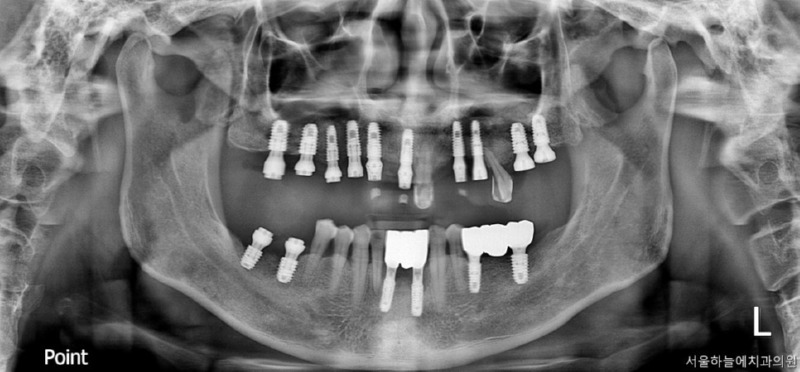

임시치아부터 최종 보철까지의 과정

수술 직후에는

임시틀니 대신 고정형 임시치아를 적용하여

일상생활과 식사 불편을 최대한 줄였습니다.

· 수술 다음 날 임시치아 장착

· 하악 일부는 2개월 내 조기 보철 완성

· 상악은 뼈이식 안정화를 충분히 거쳐 진행

전신질환이 있어

치료 기간이 길어질 가능성도 고려했으나,

6개월 내 안정적으로

보철을 마무리할 수 있었습니다.

수술 후 6개월 후 보철완료